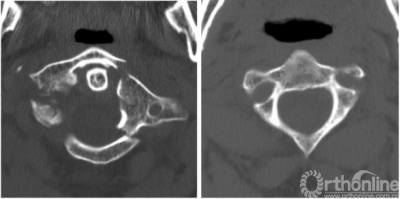

无术中或术后并发症。病人在术后12天出院。12个月后随访CT示骨折融合,未见固定不稳的征象。

无术中或术后并发症。病人术后7天出院。术后1年后的随访研究显示,尽管手术中准确地切除了疤痕组织,但在部分碎片脱位的区域没有发生骨融合。然而植入物没有发生移位,这种不稳定也没有导致临床症状出现。

No intra- or post-operative complications were observed. The patient was discharged 12 days after surgery. CT scan at 12 months follow-up revealed fracture fusion, with no signs of fixation inconsistency observed.

No intra- or post-operative complications were observed. The patient was discharged 7 days after surgery. Follow-up studies 1 year after surgery revealed no bone fusion in the area with partially dislocated fragments, despite accurate resection of scar tissue during surgery. However, the implants were not dislocated, and there were no clinical symptoms of unstable fixation.